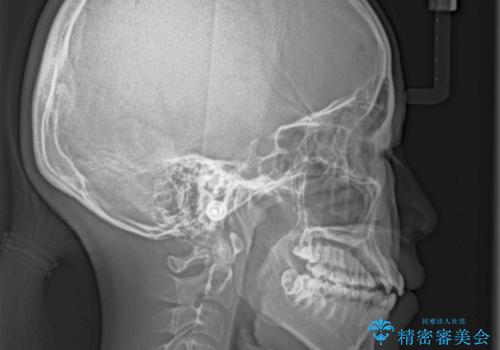

- 八重歯と上下前歯のでこぼこを気にして来院された患者様です。

上下前歯部叢生のスペース獲得のため、上下顎左右小臼歯各1歯(計4本)と全ての親知らずを抜歯して、矯正治療を行うこととしました。

上下の正中位置が大きくずれていたため、治療期間の長期化や正中が合わないまま終了することが予想されましたが、思っていた以上にスムーズに歯が移動し、満足いただける仕上がりとなりました。